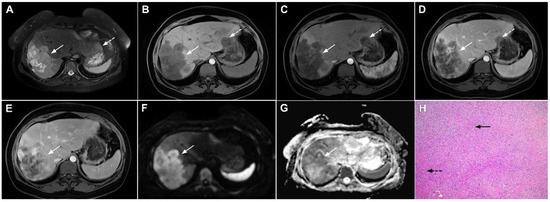

Figure 3.

Mass-forming intrahepatic cholangiocarcinoma in the left liver lobe of a 76-year-old man. Axial T2-weighted FS image shows lobulated hetrogeneously hyperintense hepatic tumor (arrow) with perilesional biliary dilatation (A). Axial diffusion-weighted image (b = 800 s/mm2) shows target-like appearance (arrow) of the lesion that consists of a central darker area and a peripheral hyperintense area (B). Corresponding ADC map is shown on (C).

If hepatocyte-selective contrast media are used, mICC presents typically as hypointense lesions on the hepatobiliary phase due to the lack of functional hepatocytes with a sharp margin between the tumor and the background liver parenchyma [7]. Thus, tumor size as well as the presence of perilesional satellite nodules, could be more precisely evaluated in the hepatobiliary phase in comparison to the MRI with conventional extracellular contrast [18,19]. Additionally, the “cloud sign”, seen as a relatively high cloud-like signal intensity in the central part of the lesion surrounded by a hypointense peripheral rim, is considered characteristic of mICC (Figure 4) [19]. The appearance of mICC in the hepatobiliary phase may be used as a prognostic factor since it correlates well with the content of intralesional fibrous stroma [20]. Namely, if cloud sign is seen it indicates a large amount of fibrous stroma in the central parts of the tumor, which is frequently associated with poor prognosis [20]. Additional imaging features, which are shown to be prognostic factors and can be assessed in the hepatobiliary phase, include capsule penetration and hepatic vein obstruction, as was demonstrated in the study by Kim S et al. [21].

Figure 4.

Mass-forming intrahepatic cholangiocarcinoma in a 68-year-old woman. Axial T1-weighted image after gadoxetic acid administration obtained in arterial phase (A) shows peripherally enhancing lesion (arrow). Portal venous phase in the same patient (B) shows progressive centripetal enhancement of the lesion (arrow) with cloud-like appearance in the hepatobiliary phase (C) consisting of an area of central enhancement and a thin, peripheral, hypointense rim.

Ancillary MRI findings that are frequently seen in mICC include peripheral biliary dilatation, capsular retraction, vascular encasement, lobar atrophy, satellite nodules, and lymphadenopathy [15,16]. Nevertheless, it should be kept in mind that in the parenchymal type of mICC, due to its origin from the small bile ducts, ancillary features such as biliary dilatation, vascular encasement, and lobar atrophy may be absent (Figure 5). In such cases, the presence of typical postcontrast behavior and capsular retraction indicate mICC. On the other hand, some degree of obstruction and peripheral bile duct dilatation is always seen in the ductal type of mICC [15].

Figure 5.

Parenchymal mass-forming cholangiocarcinoma in a 36-year-old man. The lobular slightly hyperintense lesion (arrow) is seen in the liver segment IVA in a T2-weighted image (A) with subtle capsular retraction (dashed arrow). On a plain T1-weighted image (B), the tumor (arrow) is hypointense with irregular discrete peripheral and central enhancements in the arterial phase (C), mild progressive enhancement in the portal venous phase (D), and high signal intensity in DWI (E). Hematoxylin and eosin (H&E) staining (F) showed cholangiocarcinoma (arrowhead) with poorly differentiated components (dashed arrow). Normal liver parenchyma is also shown (arrow); original magnification ×40.